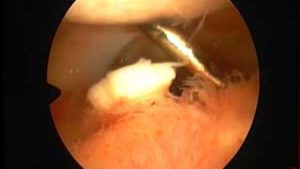

Артроскопические данные

- Наиболее частая локализация.

Крупные свободные тела локализуются в достаточно вместительных для них зонах сустава (передняя межмыщелковая область; медиальный, латеральный, заднемедиальный, заднелатеральный и верхний завороты).

Небольшие свободные тела могут легко мигрировать в тесные труднодоступные области сустава, где их тяжело обнаружить.

Большинство свободных тел при артроскопии выглядит как округлые образования бледной окраски. Форма и цвет могут указывать на их хрящевое или костно-хрящевое происхождение. Свободные тела с острыми краями формируются при свежем хрящевом или костно-хрящевом переломе и выявляются при артроскопии, выполненной в первые дни после травмы.

Свободные тела с острыми краями, находящиеся в суставе длительное время, приобретают округлую форму, что происходит не в результате трения при движении в суставе, а в результате возросшей активности фибробластов, которые заполняют неровности поверхности остроконечных фрагментов, формируя округлое свободное тело.

Артроскопия – эндоскопический метод обследования. Для этого делают 2 небольших разреза сбоку от коленного сустава. В 1 вводят артроскоп. Он оснащён камерой, которая передаёт получаемые изображения внутри сустава на большой экран. Через другой разрез вводят инструмент, который может осуществлять различные манипуляции. При небольших телах можно провести сразу их извлечение.